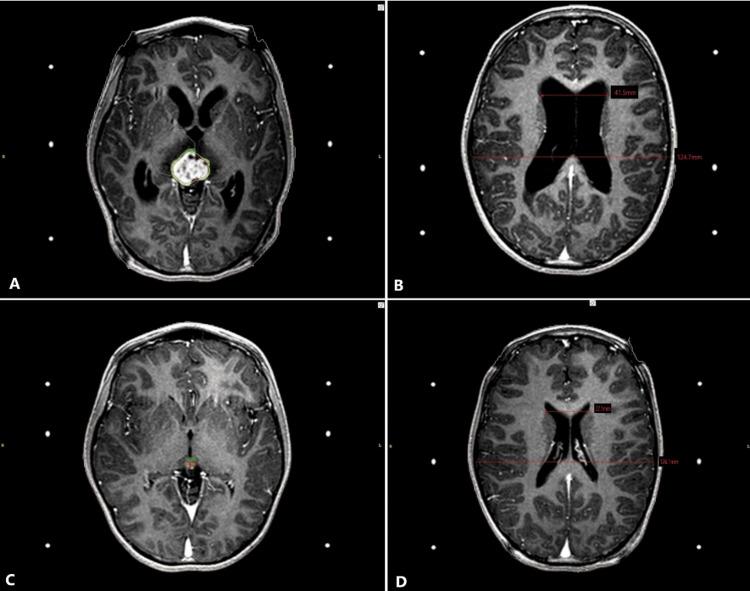

Introduction Hydrocephalus is a build-up of cerebrospinal fluid (CSF) in the brain and is characterized by abnormal dilatation of the cerebral ventricles. Patients can be either asymptomatic, have symptoms related to primary tumors, or have hydrocephalus-related symptoms. Generally, symptomatic patients are candidates for ventriculoperitoneal (VP) shunt placement to reduce acute symptoms. Little evidence exists regarding the resolution of symptomatic hydrocephalus secondary to brain tumors using stereotactic radiosurgery (SRS) alone as a primary treatment option. Methods The present study is a retrospective series of eight patients (six men and two women) diagnosed with obstructive hydrocephalus due to brain tumors treated with radiosurgery between April 2013 and February 2021. The primary endpoint of the present study is to report our institutional experience regarding the control of symptomatic obstructive hydrocephalus due to brain tumors treated with upfront radiosurgery. Results The mean age was 52 years (range, 5-79). The most common presenting symptoms included headache (100%), vision-related symptoms (75%), and ataxia (37.5%). All patients showed symptom improvement after radiosurgery, five (62.5%) patients showed resolution in less than three days and the rest of the patients resolved hydrocephalus in a longer timeframe (more than three days). All patients lowered their Evans index compared to the index documented before radiosurgery, in a range from 0.02 to 0.17. Conclusion Radiosurgery is a non-invasive alternative treatment for primary and secondary brain tumors that debut with obstructive hydrocephalus, tumors expected to have a high alpha/beta ratio might be suitable to attempt radiosurgery to avoid permanently implanted devices such as VP shunts or other invasive procedures such as a third ventriculostomy. The present study demonstrated that in selected cases SRS can lead to hydrocephalus symptom resolution along with a decrease in ventricular size in a relatively short time frame. Little evidence exists regarding the effect of SRS on symptomatic hydrocephalus resolution and further histology-specific studies are required. We acknowledge that this approach requires immediate access to radiosurgery and close clinical follow-up to ensure success.

平均年龄为52岁(范围5 - 79岁)。最常见的首发症状包括头痛(100%)、视力相关症状(75%)和共济失调(37.5%)。放射外科治疗后所有患者症状均有改善,5例(62.5%)患者在不到三天内症状缓解,其余患者在更长时间内(超过三天)脑积水得到缓解。与放射外科治疗前记录的指数相比,所有患者的Evans指数均降低,范围为0.02至0.17。

放射外科是一种针对首发梗阻性脑积水的原发性和继发性脑肿瘤的非侵入性替代治疗方法,预期具有高α/β比值的肿瘤可能适合尝试放射外科治疗,以避免永久性植入装置如VP分流术或其他侵入性手术如第三脑室造瘘术。本研究表明,在特定病例中,SRS可在相对较短的时间内使脑积水症状缓解并使脑室大小减小。关于SRS对症状性脑积水缓解的影响几乎没有证据,需要进一步进行组织学特异性研究。我们承认这种方法需要能够立即进行放射外科治疗并进行密切的临床随访以确保成功。